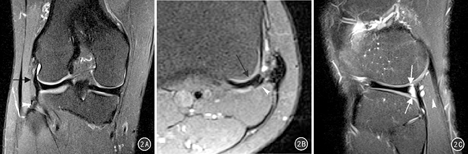

腘肌、腘肌腱的形态及走行较复杂,空间上呈螺旋状结构,冠状位及连续轴位PDWI序列图像上可清晰显示。腘肌起于胫骨近端的后内侧面,呈中等信号,向上向外延伸形成低信号的肌腱,经豆腓韧带及弓状韧带的深面,附着于股骨外侧髁腘肌沟的前方、腓侧副韧带股骨止点的前下方(图1、图2)。在斜矢状位PDWI序列观察到腘肌腱另发出细线状低信号的腘肌半月板纤维束到外侧半月板后角(图2C),与外侧半月板后角连接、关系密切。

冠状位、斜矢状位PDWI序列MRI可清晰显示其走行,腘腓韧带连接腘肌及腓骨头,起自腘肌肌肉肌腱连接部附近,向远外侧延伸,止于腓骨茎突内侧前下方接近胫腓关节处。MRI表现为自腘肌肌肉肌腱连接部向远外侧延伸,至腓骨茎突内侧前下方或腓骨头的扁平扇形低信号结构(图2),本组出现弓状韧带及豆腓韧带的膝关节均显示腘腓韧带行于其深面(图3);冠状面显示腘肌与腘腓韧带呈一锐角(图2A),这与PLC的其他结构均近乎垂直走向的特点有所不同,可以作为辨识该韧带的一个特征。